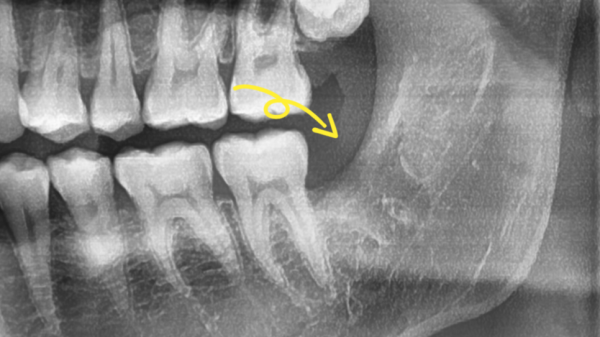

826fd3851ccac24696fbdfce7325926d_1697774670_0313.png

이부분의 통증이 아주 심해서 잠도 못자겠다고 하셨는데요.

빠른 발치가 필요하신 상황이었습니다.

해당 부분을 확대하여 보면, 뿌리가 뼈를 움켜지고있는 형태여서 발치가 쉽지 않아보였습니다.

저희 성남치과 더서울치과에서는 이러한 고난이도의 사랑니발치를

꾸준히 해 오고 있기 때문에 이날 지체하지않고 바로 발치하기로 하였습니다.

The pain in this area is so severe that you can't even sleep.

You needed a quick extraction.

If you zoom in on that part, it didn't look easy to extract because the roots were gripping the bones.

Seongnam Dental Clinic, The Seoul Dental Clinic, provides these high-level wisdom teeth

Since we have been doing it steadily, we decided to remove it right away without delay on this day.